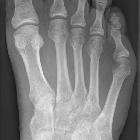

A bunionette, also known as a tailor's bunion or metatarsus quintus varus, is a bony prominence at the lateral 5 metatarsal head. It is the lateral counterpart of the more common bunion of the first metatarsophalangeal joint, and when they occur together (often with spreading of the other metatarsals), patients may be said to have a splayfoot.

Typically seen as a varus deformity at the 5 metatarsophalangeal joint. Increased angulation can also be present between the 4 and 5 metatarsals, e.g. a widening in the gap between the 4 and 5 metatarsal heads.